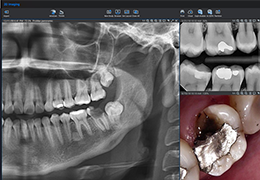

Traditional multi-planar slicing

Designed mainly for CT and MR DICOM modalities.

Multi-planar slicing.

Side-by-side comparative assessment for pre- and post-operative scans.